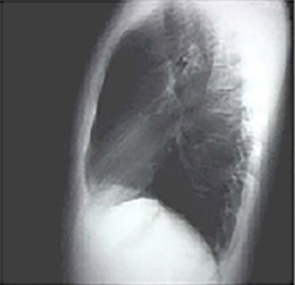

PA and Lateral

Click on the xrays to enlarge them.

Choose the best interpretation of the chest X rays in our patient:

Left ventricular enlargementand a dilated aorta

Left ventricular enlargementand left atrial enlargement

Normal

Dilated ascending aorta

Prominent aortic knob